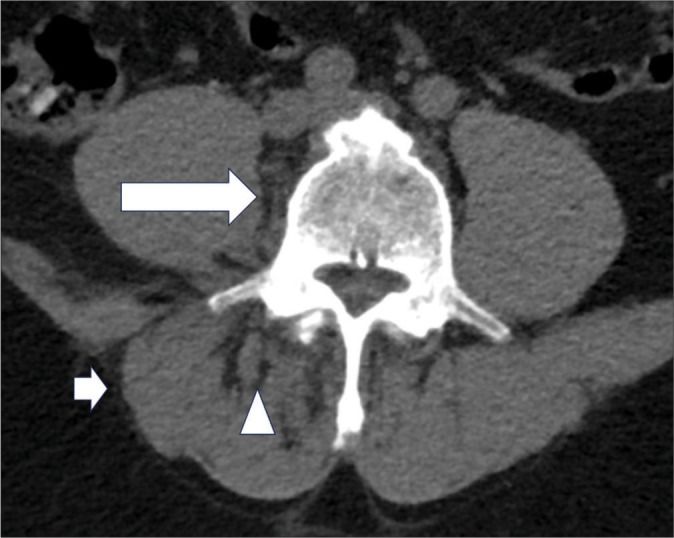

面关节化脓性关节炎是一种罕见的严重脊柱感染,但由于其临床表现和影像学表现不特异,常常被误诊。本系列病例展示了面关节化脓性关节炎患者的各种临床表现、影像学特征和预后。我们展示了不同的疾病分期,以帮助临床医生和放射科医生识别这种疾病。同时还讨论了关键的诊断误区,以提高临床实践中诊断的准确性。

Facet joint septic arthritis is a rare; yet, severe spinal infection often misdiagnosed due to its non-specific clinical presentation and radiological mimickers. This case series illustrates various clinical presentations, imaging features, and outcomes of patients with facet joint septic arthritis. We demonstrate different disease stages to aid clinicians and radiologists in recognizing this condition. Key diagnostic pitfalls are also discussed to enhance diagnostic accuracy in clinical practice.